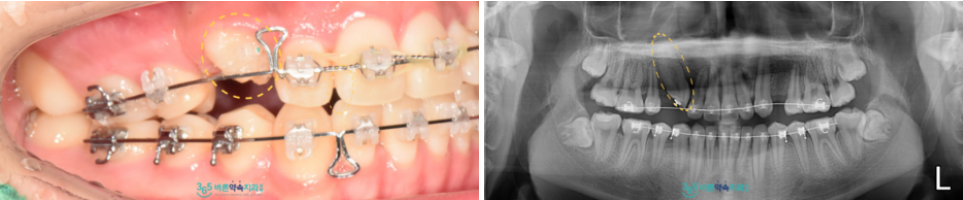

발치 후 위턱 뼈에 매복되어 있는

견치를 입천장 수술을 통해

바깥으로 드러낸 뒤

제 위치로 견인하는 과정을 진행하였는데요.

매복되어 있었던 견치가

구강 내로 모습을 드러내고

치면에 브라켓이라는 장치를

부착할 수 있을 정도가 되었을 때

와이어를 연결하여

가지런한 배열을 위한

영구치 이동을 진행하였으며,